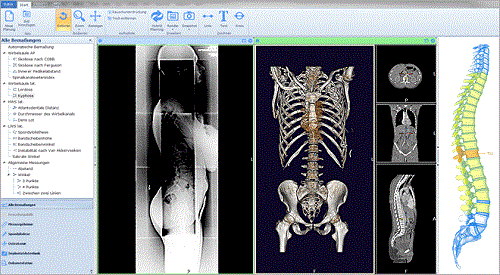

Phân đoạn tự động Mô hình xương 3D

Phần mềm mediCAD ® 3D Spine tự động phân đoạn xương từ dữ liệu trong file CT. Dữ liệu trong tệp CT của bệnh nhân được phân tích chính xác và so sánh với kho dữ liệu của phần mềm phẫu thuật chỉnh hình.

Điều này cho phép khớp tự động và phân bổ chính xác tất cả các đốt sống và đĩa được phát hiện trong tệp dữ liệu của bệnh nhân. Các đốt sống được phát hiện sẽ được mô tả bằng sơ đồ nhờ sơ đồ cột sống, Bác sĩ có thể được điều chỉnh dữ liệu bằng tay nếu cần thiết.

Việc phân đoạn tự động cực kỳ hữu ích cho việc lập kế hoạch tiếp theo, cho phép thực hiện các phép đo tự động, tự động chèn và đặt các vít ở cuống đốt sống chính xác.

Trên hình ảnh CT đã trải qua quá trình phân đoạn tự động, bác sĩ có thể tự động thực hiện và ghi lại một số phép đo thông thường:

- Đo cong vẹo cột sống theo phương pháp Ferguson

- Đo cong vẹo cột sống theo phương pháp Cobb

- Đo khoảng cách, độ cong vẹo - Kyphosis

- Đo góc đĩa đệm, chiều cao đĩa đệm

- Kiểm tra độ thoái hóa đốt sống

- Đo tính không ổn định cột sống bằng phương pháp của Van Akkerveeken

Kết quả của các phép đo đều được hiển thị trực tiếp trên Mô hình xương 3D và được ghi lại trong danh mục dữ liệu. Các phân tích dựa trên phạm vi thông thường và độ lệch dương/âm được đánh dấu bằng các màu tương ứng.

Điều này giúp bác sĩ tiết kiệm thời gian, tư vấn với bệnh nhân trực quan và chuẩn bị cho bất kỳ cuộc phẫu thuật nào nhanh chóng.